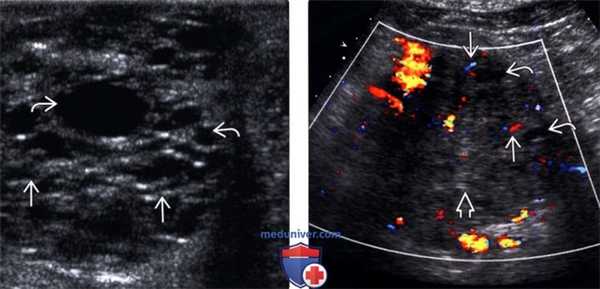

(Левый) При интраоперационном УЗИ образования поджелудочной железы на поперечном УЗ срезе определяются многочисленные мелкие кисты, разделенные линейными перегородками.

(Правый) При цветовой ультразвуковой допплерографии образования поджелудочной железы определяются центральная эхогенная зона и лежащие на периферии мелкие кисты; в разделяющих их перегородках регистрируется кровоток.